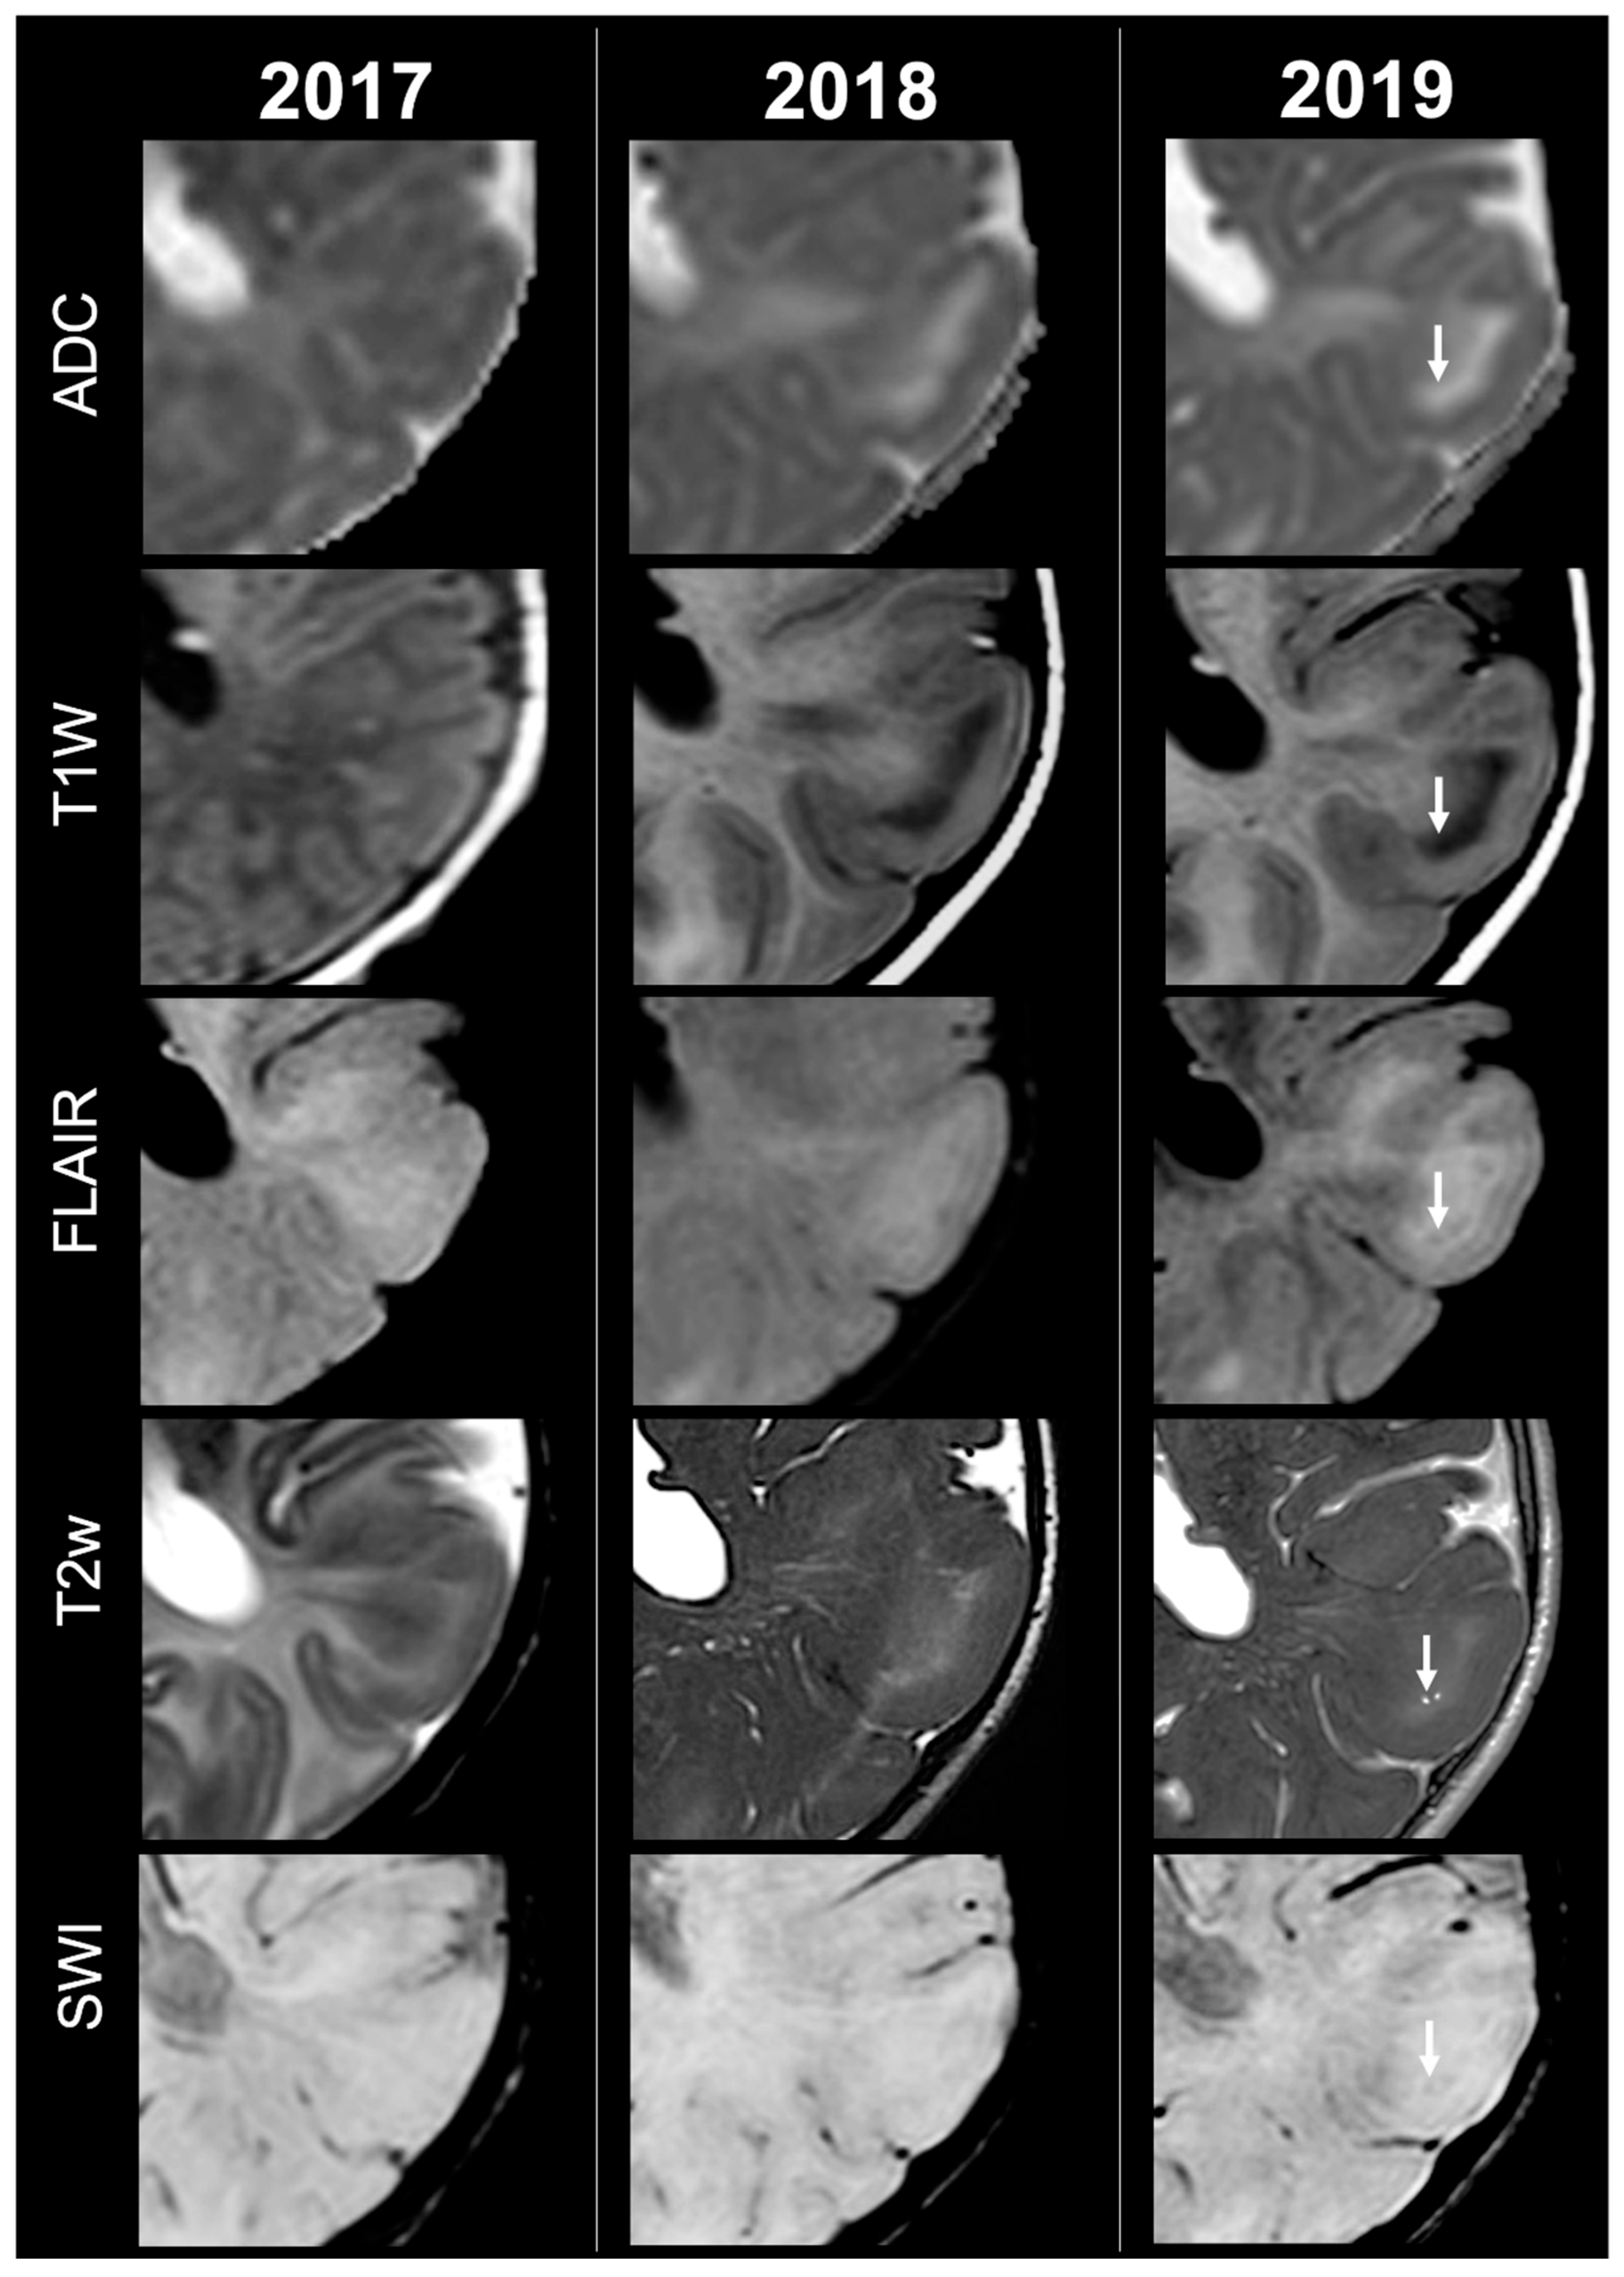

Concerning total lesion count, the interobserver agreement was excellent, with an ICC of 0.91 (95% CI: 0.87–0.95). At baseline, the total number of CTs identified across the cohort was 918 (mean ± SD = 16.1 ± 12.4), whereas at the last available MRI follow-up, the overall count increased to 1070 (mean ± SD = 18.8 ± 13.3), corresponding to a net gain of 152 CTs, equal to a relative variation of +17%. When stratified by tuber type, distinct trajectories were observed over time. Type A CTs, which were relatively abundant at diagnosis (N = 303, mean ± SD = 5.3 ± 7.0), decreased to 255 (mean ± SD = 4.5 ± 5.9) at follow-up, yielding a reduction of 48 lesions (−16%). Conversely, type B CTs showed an opposite trend, increasing from 438 (mean ± SD = 7.7 ± 8.4) at baseline to 556 (mean ± SD = 9.8 ± 8.6) at follow-up, corresponding to a net increase of 118 tubers (+27%). An example of MRI signal evolution from tuber A to tuber B is shown in Figure 1. Similarly, type C1 CTs rose from 160 (mean ± SD = 2.8 ± 4.8) to 220 (mean ± SD = 3.9 ± 5.8), with a net gain of 60 tubers (+38%). Type C2 CTs, initially rare at diagnosis (N = 14, mean ± SD = 0.2 ± 0.8), markedly expanded to 33 (mean ± SD = 0.6 ± 1.5), accounting for an increase of 19 CTs (+136%). Finally, type D CTs were only sporadically encountered, with a modest increase from 3 (mean ± SD = 0.1 ± 0.3) to 6 (mean ± SD = 0.1 ± 0.4), equating to a 100% variation. The observed increment of type C2 tubers was attributable almost exclusively to the progressive transformation of pre-existing type B lesions and, more prominently, type C1 lesions, while the increase in type C1 tubers reflected the gradual conversion of both type A and type B CTs that were already detectable at disease onset. An example of MRI signal evolution from tuber B to C1 is shown in Figure 2, while from tuber C1 to C2 in Figure 3. Only in one patient was a type C1 tuber newly identified at follow-up without clear evidence at baseline. In contrast, newly apparent tubers emerging over time but not clearly visible on baseline scans were most frequently represented by type A and type B lesions. Type D tubers were rare overall and were identified in only six lesions from four patients with a particularly high lesion burden; in all but one case they represented the evolution of type A or type B CTs (an example of MRI signal evolution from tuber A to tuber D is shown in Figure 4), while in a single case they were associated with adjacent subtle calcific foci. Overall descriptive data are summarized in Table 1.

Figure 3.

Left occipital tuber transition from type C1 to C2 at three different timepoints in a female patient diagnosed with TSC1.